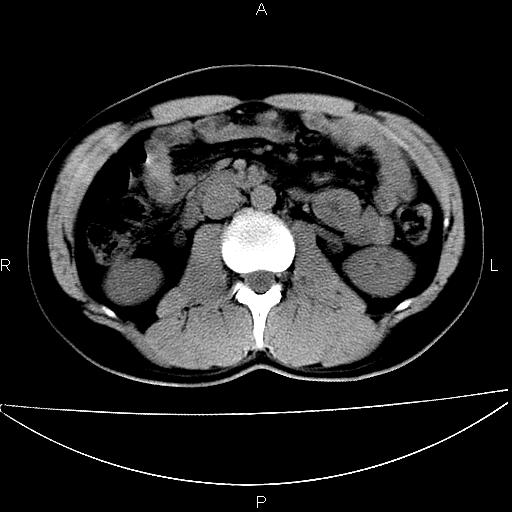

男 25岁 自述 尿频尿急,排尿困难20多天.无腰痛, b超说左肾盂轻度积水,左输尿管上端扩张.未见结石影. ct我看双侧肾盂轻度积水,双输尿管上端都扩张,大家看看能看见结石吗?

双肾轻度积水,双侧输尿管上段扩张(原因待查)。

考虑肾外肾盂 前列腺轻度肿大 密度欠均 考虑炎性改变

箭头所指不是输尿管,壶腹型肾盂。

肾外肾盂,必要时+c